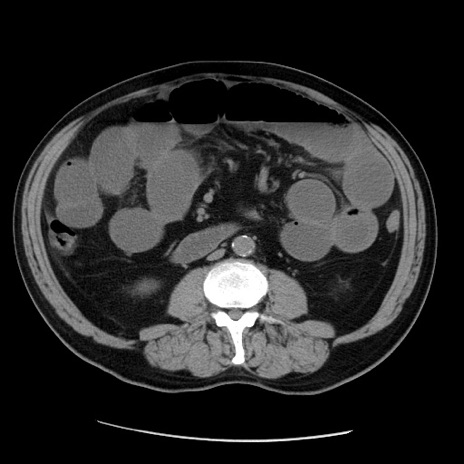

症例20(横断像)

【症例】 60歳代男性

【主訴】 腹部膨満、嘔吐

【現病歴】5日前頃より倦怠感を認め食事量減少し4日前の朝嘔吐、食事摂取困難となった。 3日前近医受診し点滴施行され整腸剤などを処方された。 当日他院を受診し、腹部膨満著明、炎症反応の上昇(CRP10.8、WBC11200)あり、紹介受診となる。

【身体所見】 意識JCS1 受け答えがはっきりしないBP 111/57mHg、 P 67bpm、、BT35.2°C、SpO2 97%(RA)、 腹部:膨隆、打診で鼓音あり、全体的に圧痛有り、腸蠕動音(-)、反跳痛ははっきりせず。

【データ】WBC 11400、CRP 14.20